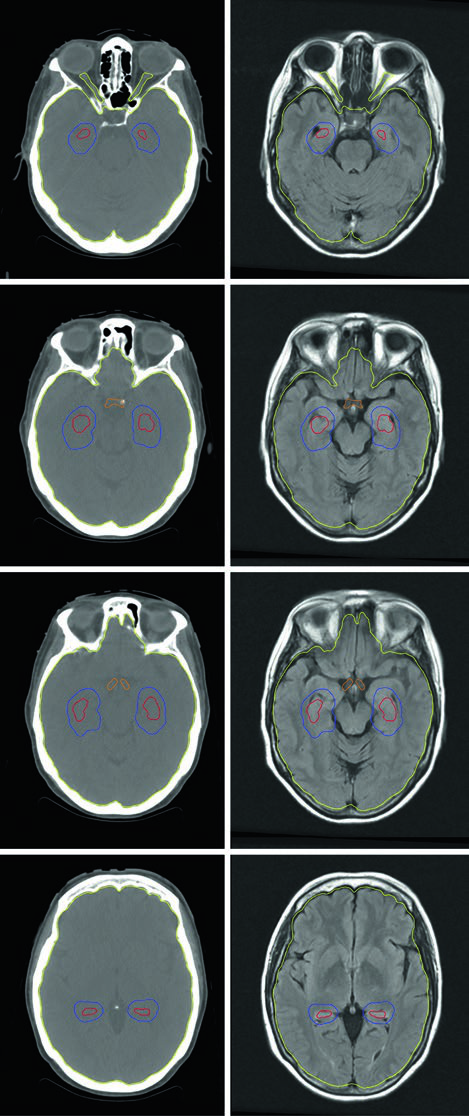

O planejamento da HA-WBRT requer IMRT com planejamento inverso, usando TC de planejamento fusionada com RM contrastada com gadolínio. A sequência utilizada é spoiled gradient tridimensional com espessura de corte axial de 1,25–1,5 mm para definir a região de exclusão hipocampal com precisão adequada. Segundo as diretrizes de contorno do RTOG 0933, apenas a porção SGZ dos hipocampos é contornada (não a estrutura inteira), e uma expansão volumétrica de 5 mm é aplicada para criar a zona de exclusão. O PTV consiste no tecido cerebral inteiro (parênquima até o forame magno) menos os hipocampos expandidos, sem margem de setup adicional.

As restrições de dose são rigorosas e variam conforme a indicação. Para metástases cerebrais: hipocampos D100% ≤9 Gy, Dmax ≤16 Gy; nervos ópticos e quiasma Dmax ≤30 Gy. Para PCI de SCLC com preservação hipocampal, os limites ficam ainda mais apertados: hipocampos D100% ≤7,5 Gy, Dmax ≤13,5 Gy; nervos ópticos e quiasma Dmax ≤25 Gy. Uma limitação importante que precisa ser avaliada na seleção do paciente: lesões localizadas a menos de 5 mm do hipocampo excluem o paciente da HA-WBRT.

O Método 2 de Soliman et al. é mais conservador e tende a gerar volumes de CTV maiores. No exemplo da figura, uma cavidade de 24 mm no lobo temporal esquerdo — após ressecção total de metástase de 33 mm de câncer retal primário com contato dural pré-operatório mas sem contato com seio venoso — receberia margem de 10 mm ao longo do retalho ósseo. A fração única foi escolhida pelo tamanho pequeno da cavidade (<3 cm) e distância suficiente de estruturas cerebrais delicadas. No Gamma Knife, PTV = CTV sem expansão adicional. O Método 1 (Soltys) aplica simplesmente 2 mm uniformes ao redor da cavidade visualizada na RM T1 pós-gadolínio, resultando em volume menor e potencialmente menos toxicidade.